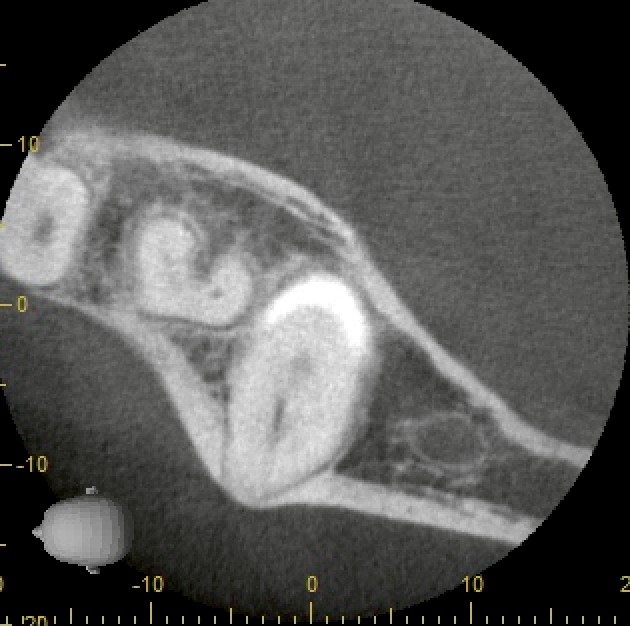

CTで詳しく確認すると、

* 歯冠は舌側(内側)

* 歯根は頬側(外側)

に位置する、通常とは逆向きに埋まった「逆性歯」であることが分かりました。

CT画像をさらに詳しく見ると、

* 親知らずの周囲に透過像(黒く見える部分)

* 感染による炎症の可能性

* 含歯性嚢胞(歯に関連した嚢胞)の疑い

が認められました。